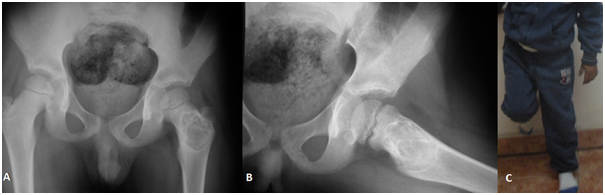

Follow up ranged from 18 months to 4 years for all patients. Close follow up until clinical improvement and radiological consolidation of the cyst. Pain Score according to Healing time ranged from 21 - 90 days with average 42.2 days. Motion of the arm as patients can move their arm without pain was allowed. Weight bearing for the lower limbs also had been allowed as patients felt pain subsided even there is no complete healing radiological. Painless non supported gait was observed and normal full activity with returning to their ordinary activities for all patients. Sports activities like football and running were return to normal in 7 children five out of them had tibial cyst (Figures 2 & 3) and other two patients had proximal femoral cyst (Figures 4 & 5) were returning to their normal sport activities. VAS ranged from 3-9 with average 5.7 which was improved to average 1.5 at final follow up (Figure 6). At final radiological evaluation we found all cases had consolidated felling of cysts by bony tissue in X-ray film and continuity of the cortical osseous structures. No cases of recurrence were observed for the last follow up of all patients.

Figure 5 Follow up 3months Plain X-Ray with consolidated bone and patient can stand on his affected limb.